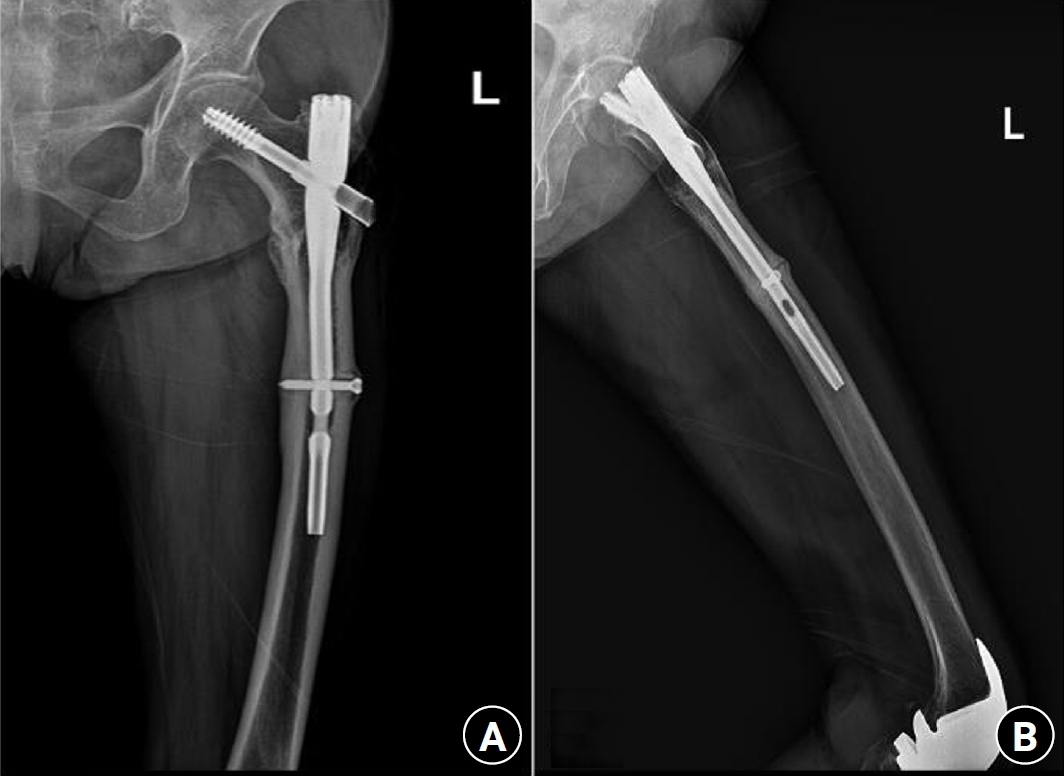

Fig. 6.

Prefracture radiographs of a 73-year-old female patient who subsequently presented with a femoral shaft fracture demonstrating cortical hypertrophy and microfracture. (A) Anteroposterior view. (B) Lateral view.

Fig. 7.

Radiographs of the same patient with a femoral shaft fracture and implant failure. (A) Anteroposterior view. (B) Lateral view.

Case 3: distal locking screw of intramedullary nail

A 73-year-old female patient visited our emergency room complaining of pain in the left thigh that had begun approximately a month ago. She had undergone intramedullary nail fixation for a left femoral intertrochanteric fracture 9 years prior and reported no history of recent trauma. The patient had initially sought treatment at another hospital for her left thigh pain and was discharged after conservative management. However, she experienced sudden severe pain accompanied by a breaking sound while walking. Upon examination, her BMD at the L3‒4 levels was noted to be ‒3.1. The patient also had a history of rheumatoid arthritis and hypertension, with no history of cancer. Radiographic evaluations, including anteroposterior and lateral views of the left femur, revealed a left femoral shaft fracture and metal breakage at the distal locking screw fixation site of the previously inserted intramedullary nail. Notably, when the patient first visited the other hospital, a hypertrophy and microfracture were observed at the lateral site of the distal locking screw insertion (Figs. 6, 7). Following the diagnosis, the patient underwent intramedullary fixation using a long nail. Subsequent follow-up evaluations indicated successful bone union at the fracture site.

All three patients had no history of taking bisphosphonates. Hypertrophy of the femur lateral cortex was observed at the fracture site in all three patients. The first patient with synostosis of the hip joint had no range of motion of the right hip joint. As the weight-bearing force was not properly distributed during walking, femur lateral bowing was induced, and tensile force was continuously applied to the lateral cortex of the proximal femur. The second patient had an underlying disease of osteogenesis imperfecta. As a result, the weakened femur showed lateral bowing, and similarly, tensile force acted upon weight-bearing. The other patient underwent intramedullary nail fixation due to a previous femoral intertrochanteric fracture. As the distal locking screw of the intramedullary nail exerted a sustained tensile force on the femur lateral cortex, hypertrophy also occurred around the distal locking screw head.